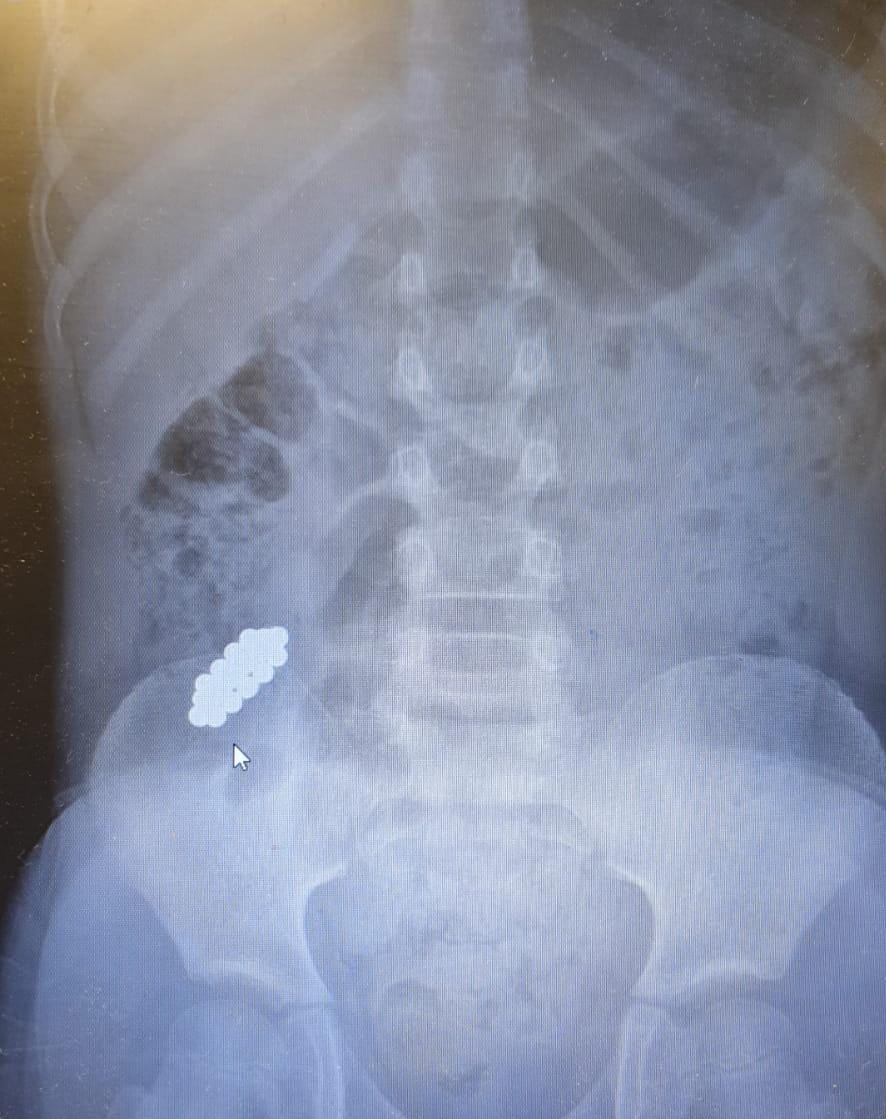

"בצילום נצפו המגנטים במעי הדק במקום שלא ניתן להגיע ללא ניתוח. הוחלט כי נעשה מעקב לבחון את מקומם ובשלב מסוים נמצא כי הם אינם מתקדמים לבד ויש לעשות קולונוסקופיה. המגנטים נמצאו במעי הגס והוצאו בהצלחה".